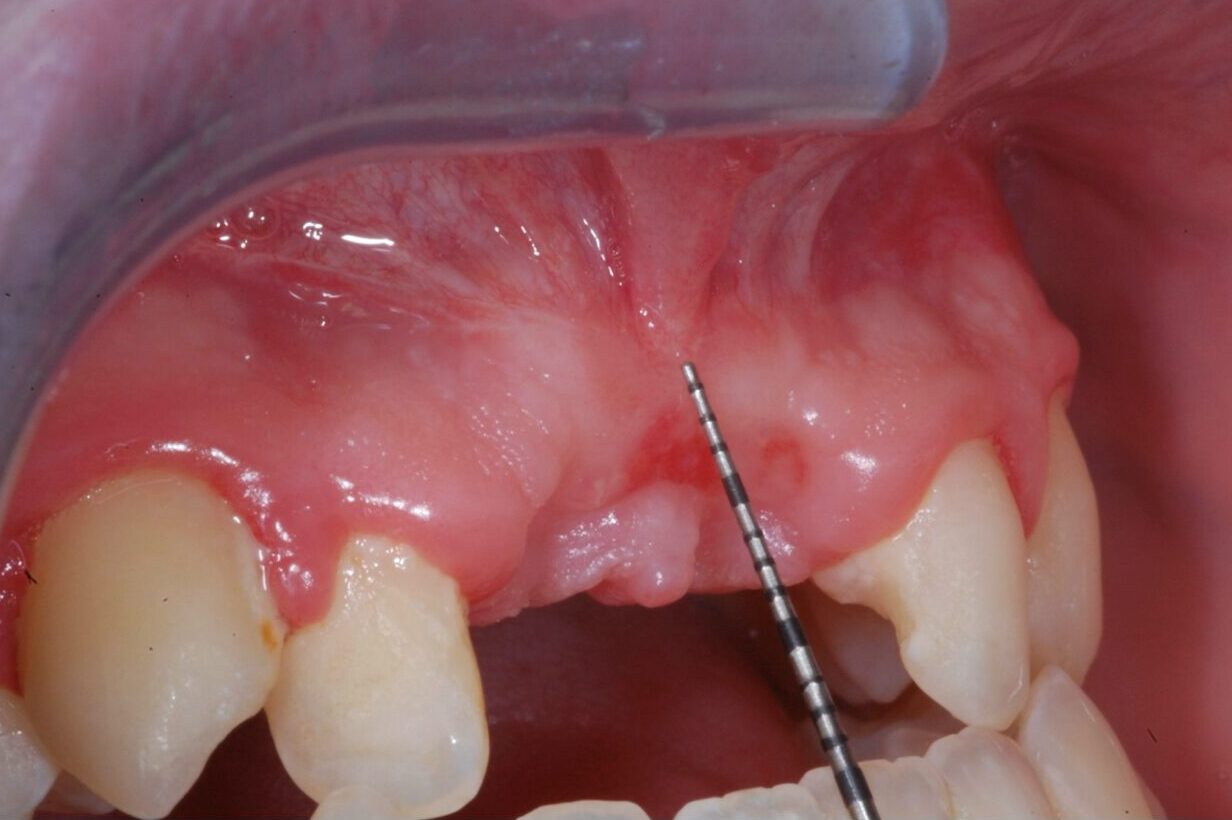

• LE RIAPERTURE, GESTIONE DEI TESSUTI MOLLI, INNESTI DI TESSUTI MOLLI

• TERAPIA IMPLANTARE DEI SETTORI ANTERIORI

• PROTOCOLLI CHIRURGICI NELL’ INSERIMENTO

DELL’ IMPIANTO POST ESTRATTIVO IMMEDIATO E

DIFFERITO A MEDIO E LUNGO TERMINE